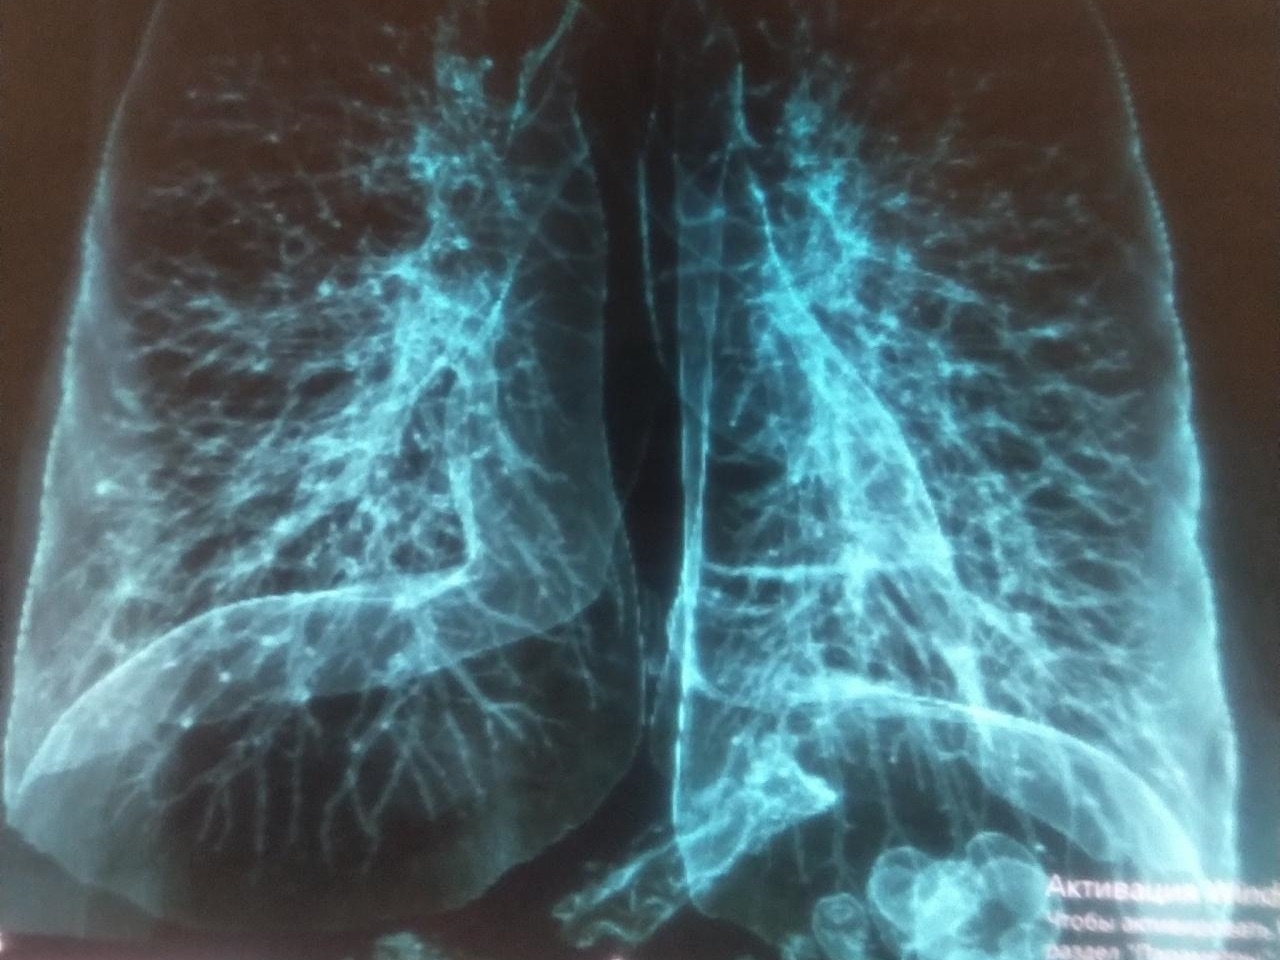

※ 普通の人の「肺」